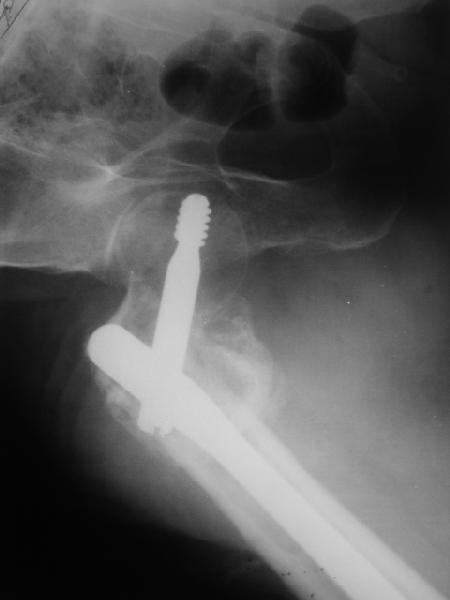

Уважаемые коллеги! Нужен совет.Больной Х., 21 год, ДЗ: ложный сустав вертельной области правого бедра.

Травма 8 мес. назад, ДТП, получил закрытый межвертельный перелом правого бедра. Лечился в городской больнице одного из городов-спутников г. Караганды скелетным вытяжением в течение 3 недель, затем кокситной гипсовой повязкой 2 мес. В настоящее время имеется укорочение конечности на 7 см, умеренная боль в вертельной области; ходит без костылей, полностью нагружая больную конечность, при нагрузке отмечается смещение дистального отломка проксимально примерно на 1,0 см.; объем движений в коленном суставе сохранен; при пальпации отломков боли нет, умеренная патологическая подвижность. Планируем внеочаговый остеосинтез спице-стержневым аппаратом, дистракция до восстановления длины бедра, вторым этапом остеосинтез стержнем Гамма. Есть надежда, что на дистракции пойдет сращение и у больного хватит терпения завершить лечение в аппарате.

Снимки были в приложенном pdf файле. Сейчас они выложены отдельно, вверху исходного сообщения. Если их не видно, перезагрузите страничку.

В приложении пример пациента, близкого по картине к тому, что представил Виктор (варус и смещение периферического отломка на поперечник кзади). Сделали как раз то, что Виктор исходно намеревался - аппаратная коррекция и затем гамма.